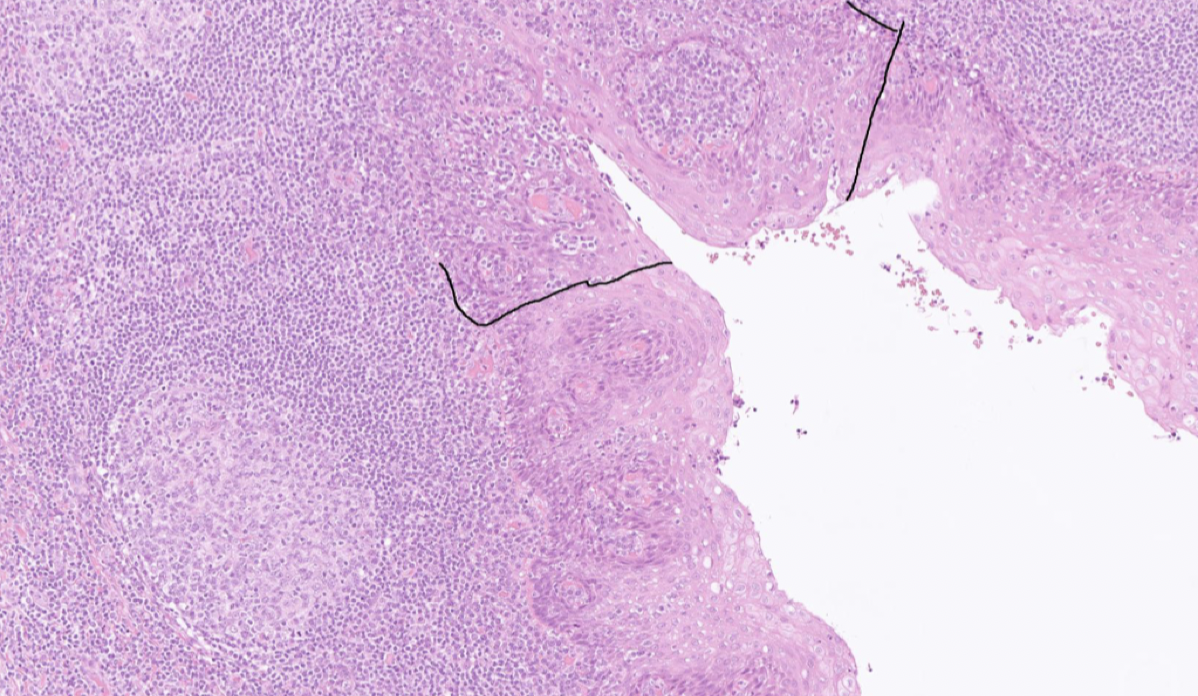

Vilken struktur har lymfnoder?

Inkapslade strukturer med fibrösa kapslar. Under kapseln finns ett sinus där afferenta lymfkärl tömmer sig med DC. I sinuset finns makrofager.

Ytterst finns ett cortex med folliklar berikat med B-celler. Folliklarna kan antingen ha ett GC eller inte.

Sedan finns ett parafollikulärt cortex med mestadels T-celler. De kommer dit via HEVs.

Hur ser en aktiverad lymfnod ut?